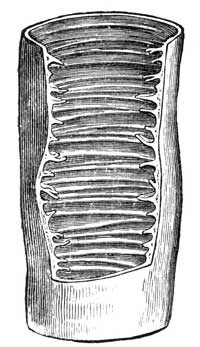

If it cannot well be bathed, let it be fomented by a large piece of flannel soaked with boiling water, and placed round the diseased part. We have seen a wasting bone healed entirely in a few weeks by this means. We have seen a man with the bones of both his legs splintering off and coming through the skin perfectly healed in a few months. It stands to reason that it should be so. The bathing in his case, like the fomenting in others, were so effectually done that the bones themselves were heated, and strong healing action set in at once. We saw lately a piece of dead bone above four inches long come out of a young man's arm as the result of nothing else but fomentation. The arm was soon as whole and as useful as could be desired, though it had been to all appearance only fit to be taken off at the elbow. The steady supply of moist heat does wonders in this way.

We have seen some most remarkable specimens of what was erroneously thought sufficient fomentation. One was a case of diseased thigh-bone. A bit of old flannel, about a quarter of a yard square, had been wrung out of water slightly tepid and laid on the skin, covered by a little cloth scarcely equal in size. The application would not have conveyed activity to the skin on which it was laid, though it required to convey it to the heart of a large mass of bone. The helpless complaint of the operator was that it did no good. How in the world could it do good? Not less than six or seven or even eight yards of a blanket are required. That is to be folded and rolled up so that a good quantity of boiling water may be poured first into one end of it and then into the other. It has to be squeezed and kneaded till the heated water and steam are fairly soaking the inside of the blanket. When this is opened up, it is far too hot to put to the skin, but a double flannel or strong towel may be put on first, so that the heat shall go gradually through to the body, and by-and-by into the bone. This may be done at least once a day—if agreeable, it may be done twice. But it must be so well done that the heat shall effect the bone, or you cannot look for any result of importance.

Preparing Blanket for Fomentation.

In the case of hip-joint disease, the armchair fomentation (see) is the best form of fomenting. For other parts, common sense will guide how to produce an extensive and thorough heating of the diseased part and its neighbourhood by some similar means (see Bathing the Feet; Pains, etc.). It is only heating the failed tissues, only keeping on such heating, and all the elements of perfect cure are supplied. Even limbs which have shrunk and become shorter, grow out to their natural size under this patient heating.